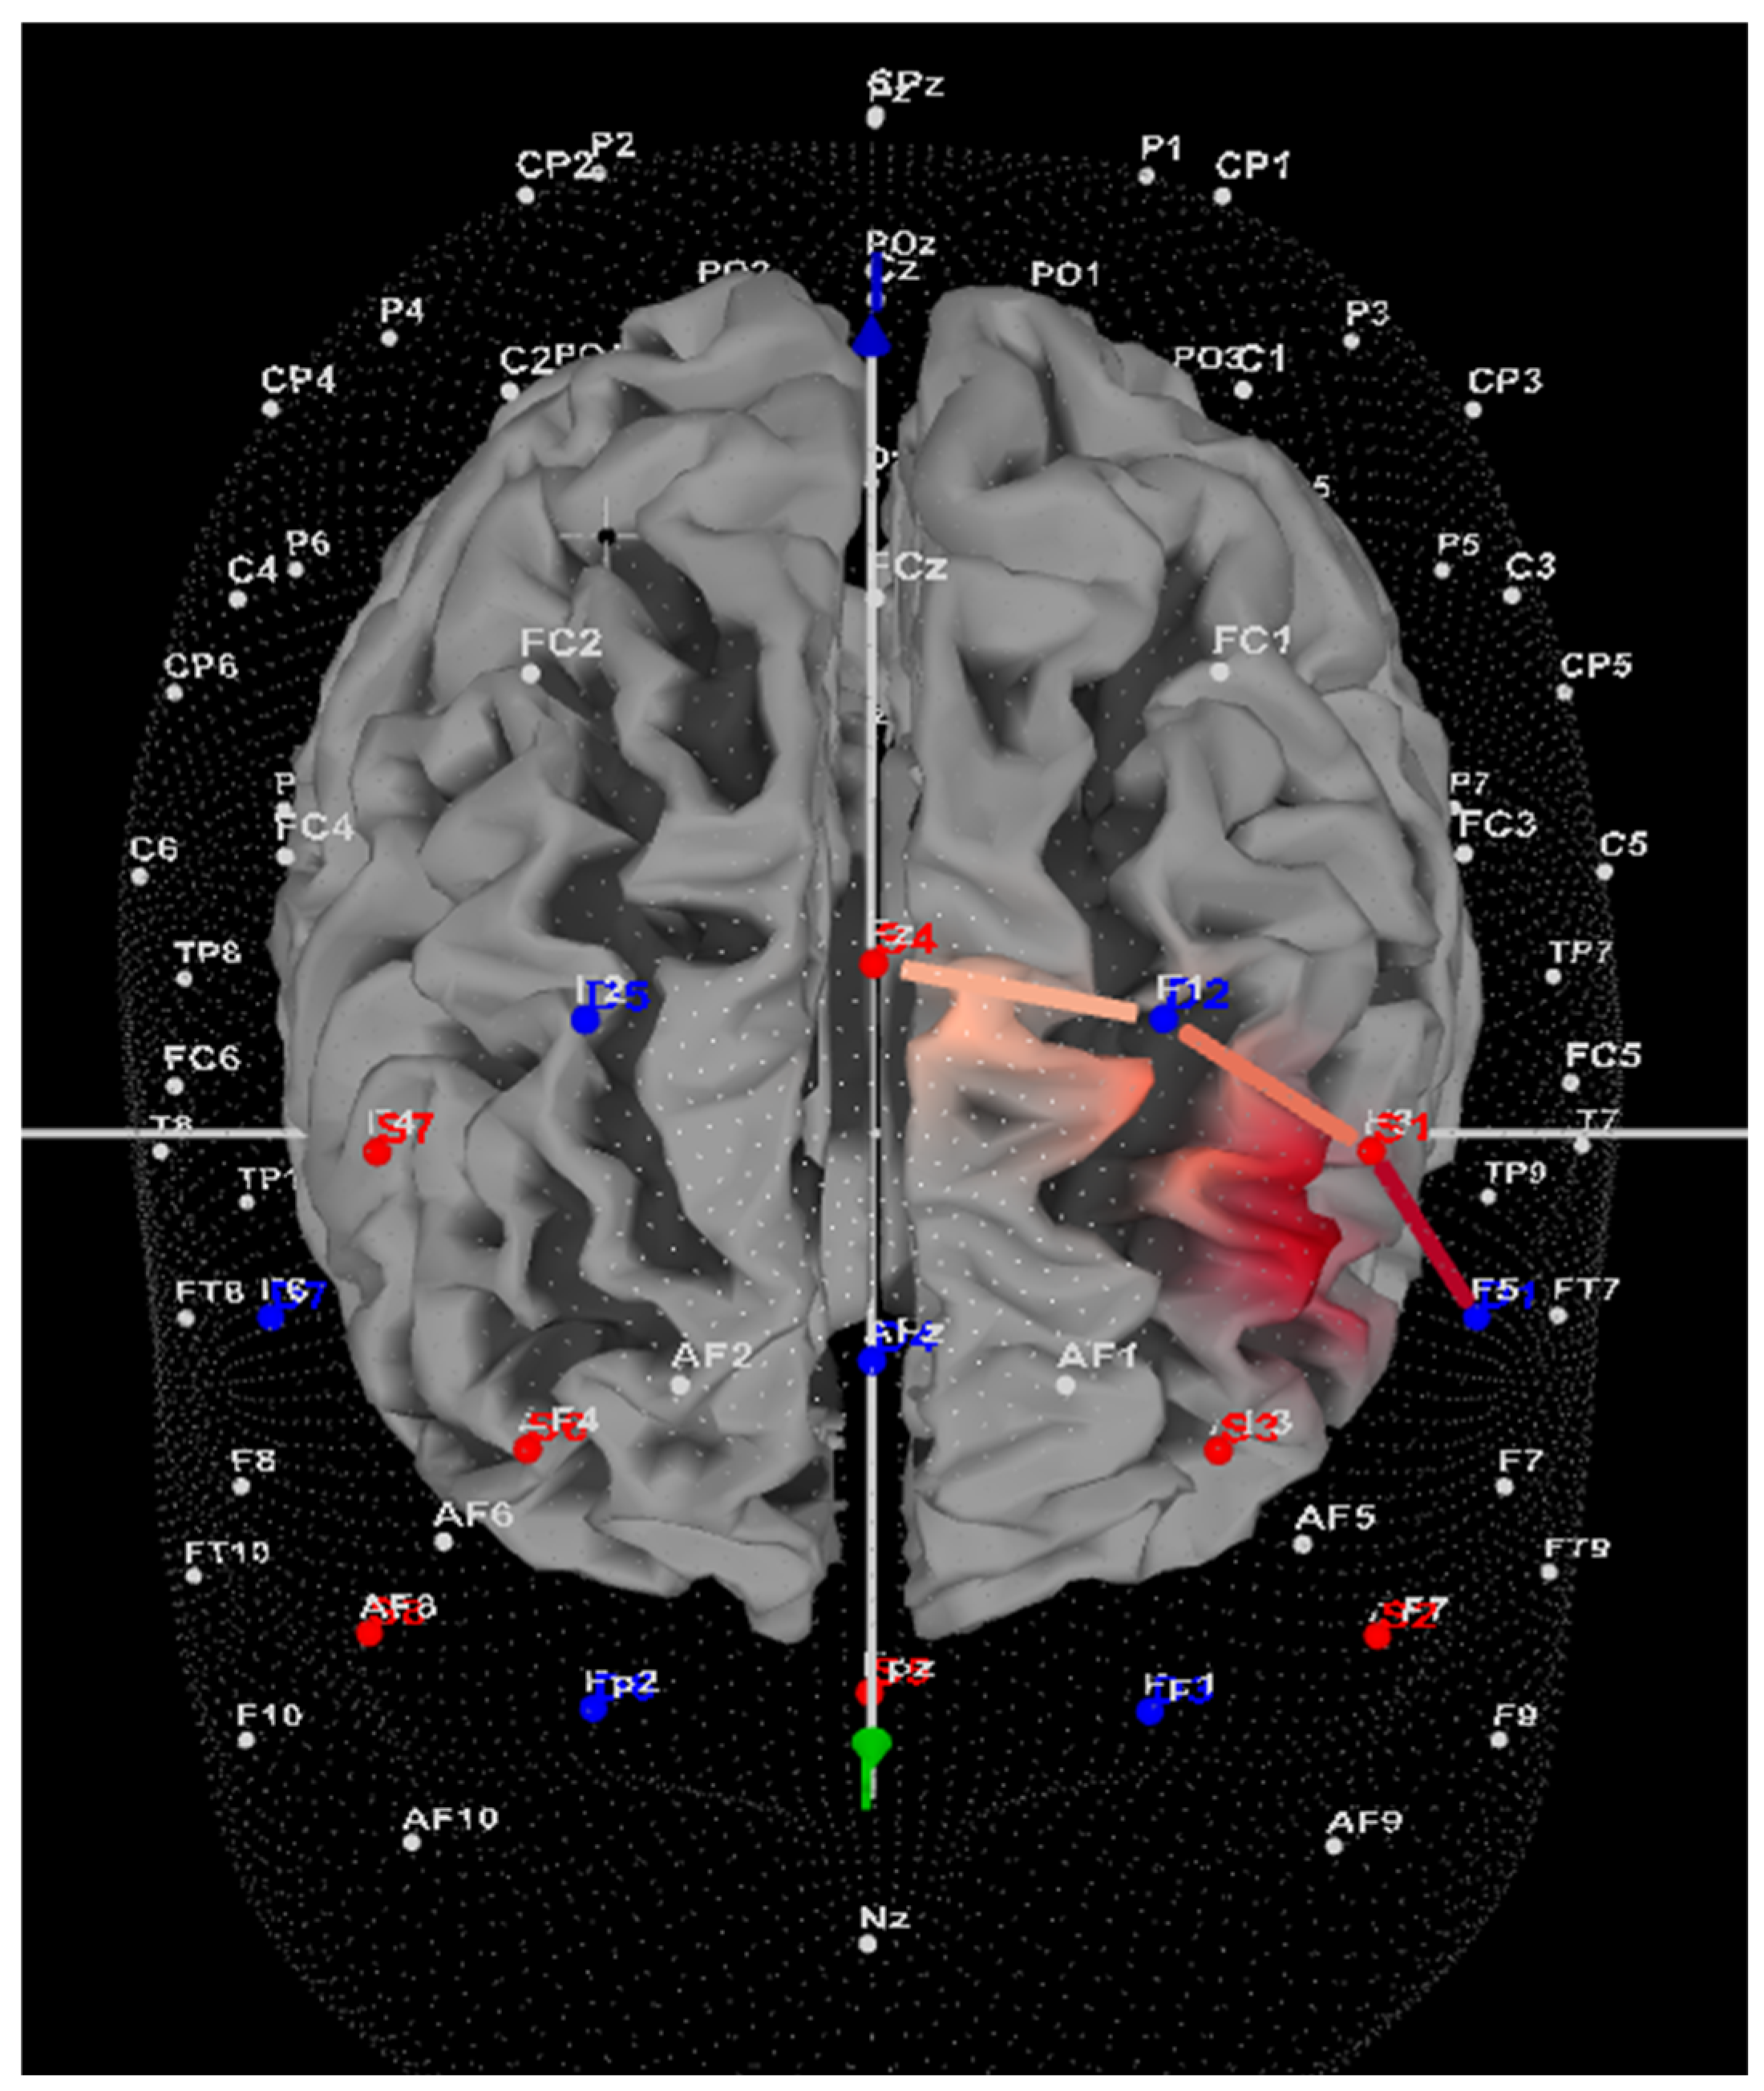

2.3.2. fNIRS and Left DLPFC Activity

3.3. fNIRS: Left DLPFC Oxygenation